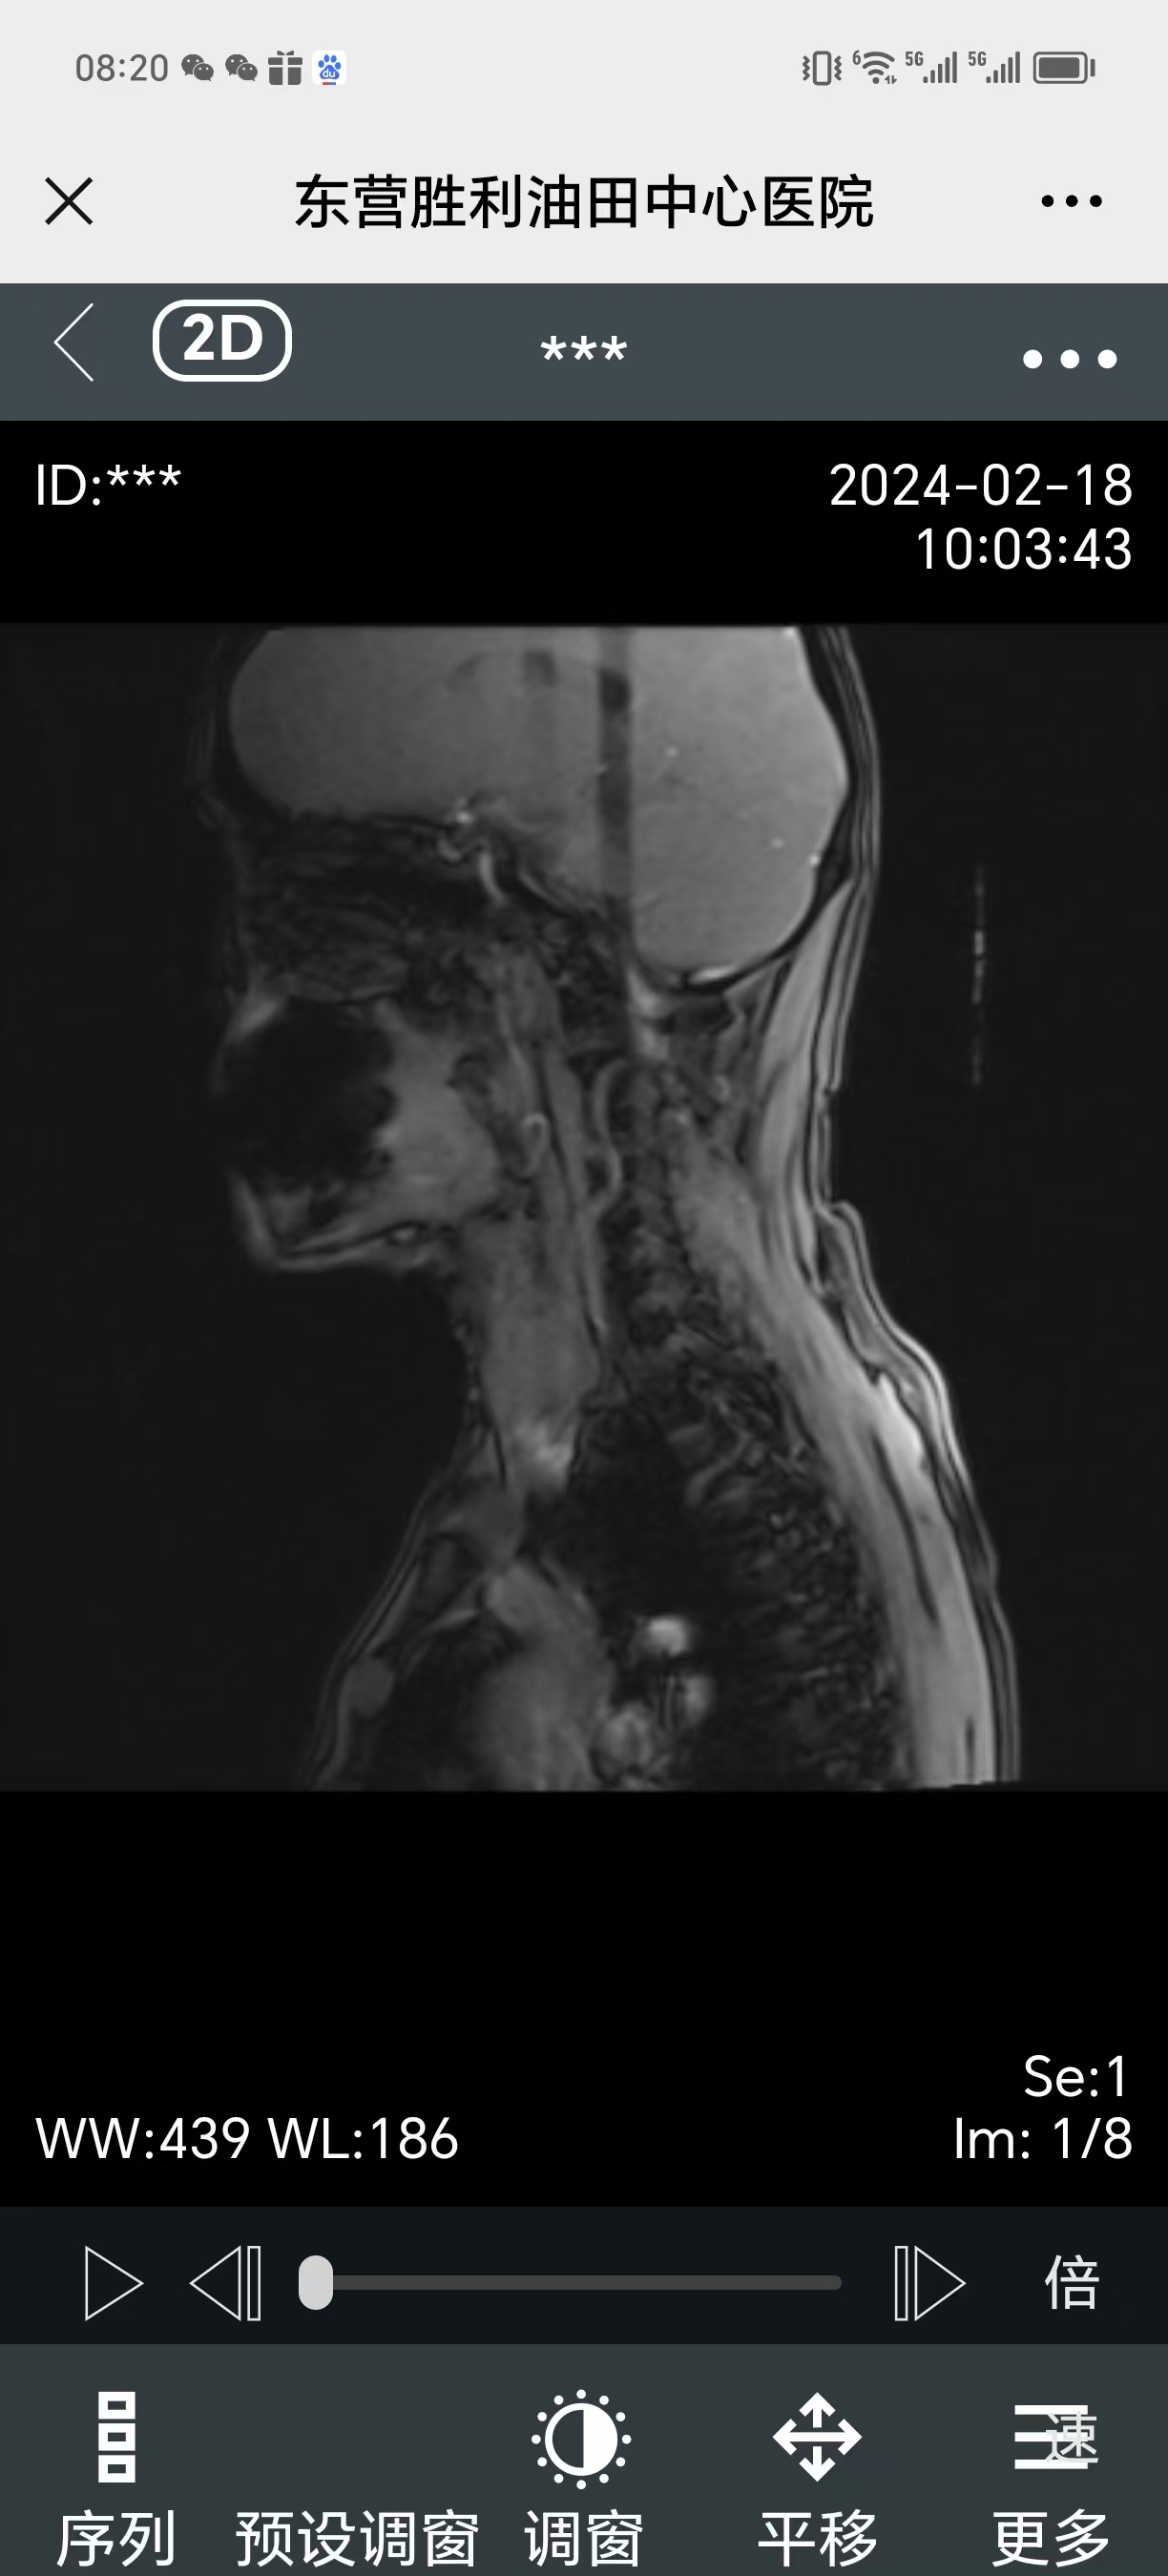

• 2024.02.18,复查,症状还在。